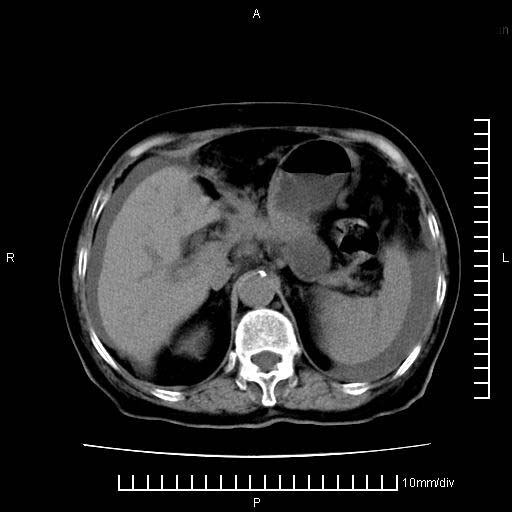

上腹疼痛月余,外院核磁诊断胰腺癌。现临床示右下腹可明显触及包块,可片子上怎么没有看到?

1.胰腺颈体部癌。

2。腹腔积液。

3。右胸腔积液,伴右肺下叶部分萎陷。

4。右肾盂囊肿。

胰腺体部癌累及周围器官,腹膜、粘连

1。胰腺ca伴腹膜腔转移

2。肝左叶低密度灶,考虑转移可能

胰腺体部癌累及周围器官,腹膜、粘连,临床摸到的可能是粘的组织

胰腺结构模糊,胰尾部见囊性包块,周围脂肪密度增高,左肾前筋膜增厚,胸水、腹水。不符合胰腺ca伴腹膜腔转移。考虑胰腺炎伴假性囊肿形成、胸腹腔积液。

右肾盂囊肿。

1)考虑胰腺癌并胰腺假性囊肿形成。2)肝内低密度灶,不排除转移。3)右肾盂积水。4)腹水。5)右侧胸腔积液并右肺下叶部分膨胀不全。

考虑胰腺ca伴腹膜腔转移、肝左叶转移、右肾积水。右胸腔积液。